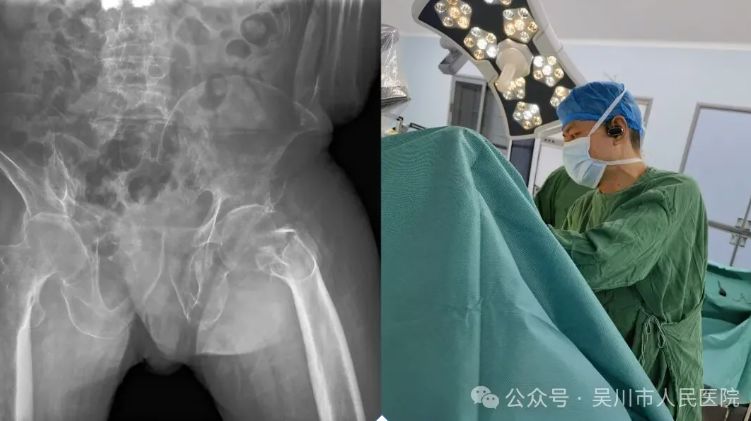

一名因车祸导致全身多处严重创伤的患者被送至我院时,已处于意识模糊、血压骤降的危险状态,诊断为多发性骨盆及股骨粉碎性骨折,伴有失血性休克,生命垂危。

创伤中心立即启动应急机制,急诊医学科迅速开通创伤绿色通道,院领导现场指挥调度,骨外科一区、麻醉科、重症医学科、输血科等多学科团队迅速集结,投入抢救。

医护团队果断采取“先保命,再治伤”的阶梯方案:先行骨科干预稳定骨折、控制出血,快速输血补液纠正休克,待生命体征平稳后,再行精准复位内固定手术。由曾文晓副主任医师、王井旺主治医师、李斌医师组成的手术团队争分夺秒、高效协作,顺利完成手术。术后患者转入ICU严密监护,经个性化治疗与护理,现已脱离生命危险,正在逐步康复中。